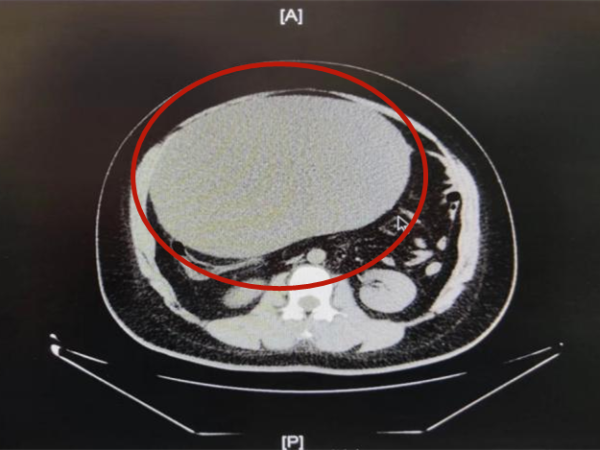

腹部快速肥胖时, 你以为这是单纯的发胖? 不不不 这有可能是肿瘤在快速生长, 一起来看看晓琪(化名)的经历: 近日,21岁的晓琪在早上上完厕所后, 突然腹痛难忍....